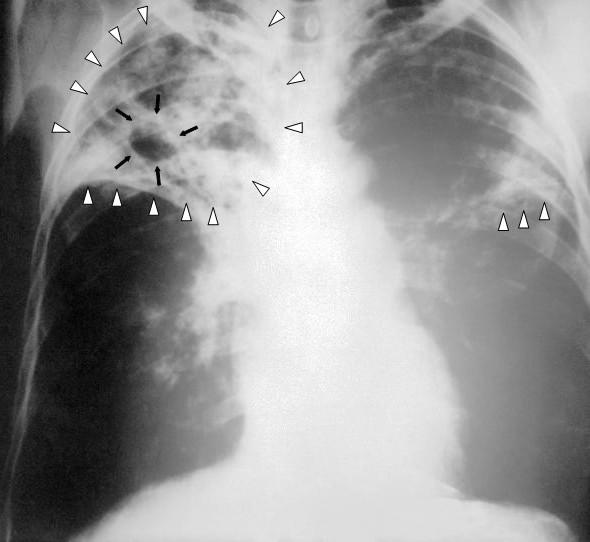

Sarcoidoza: înțelegere, simptome și management